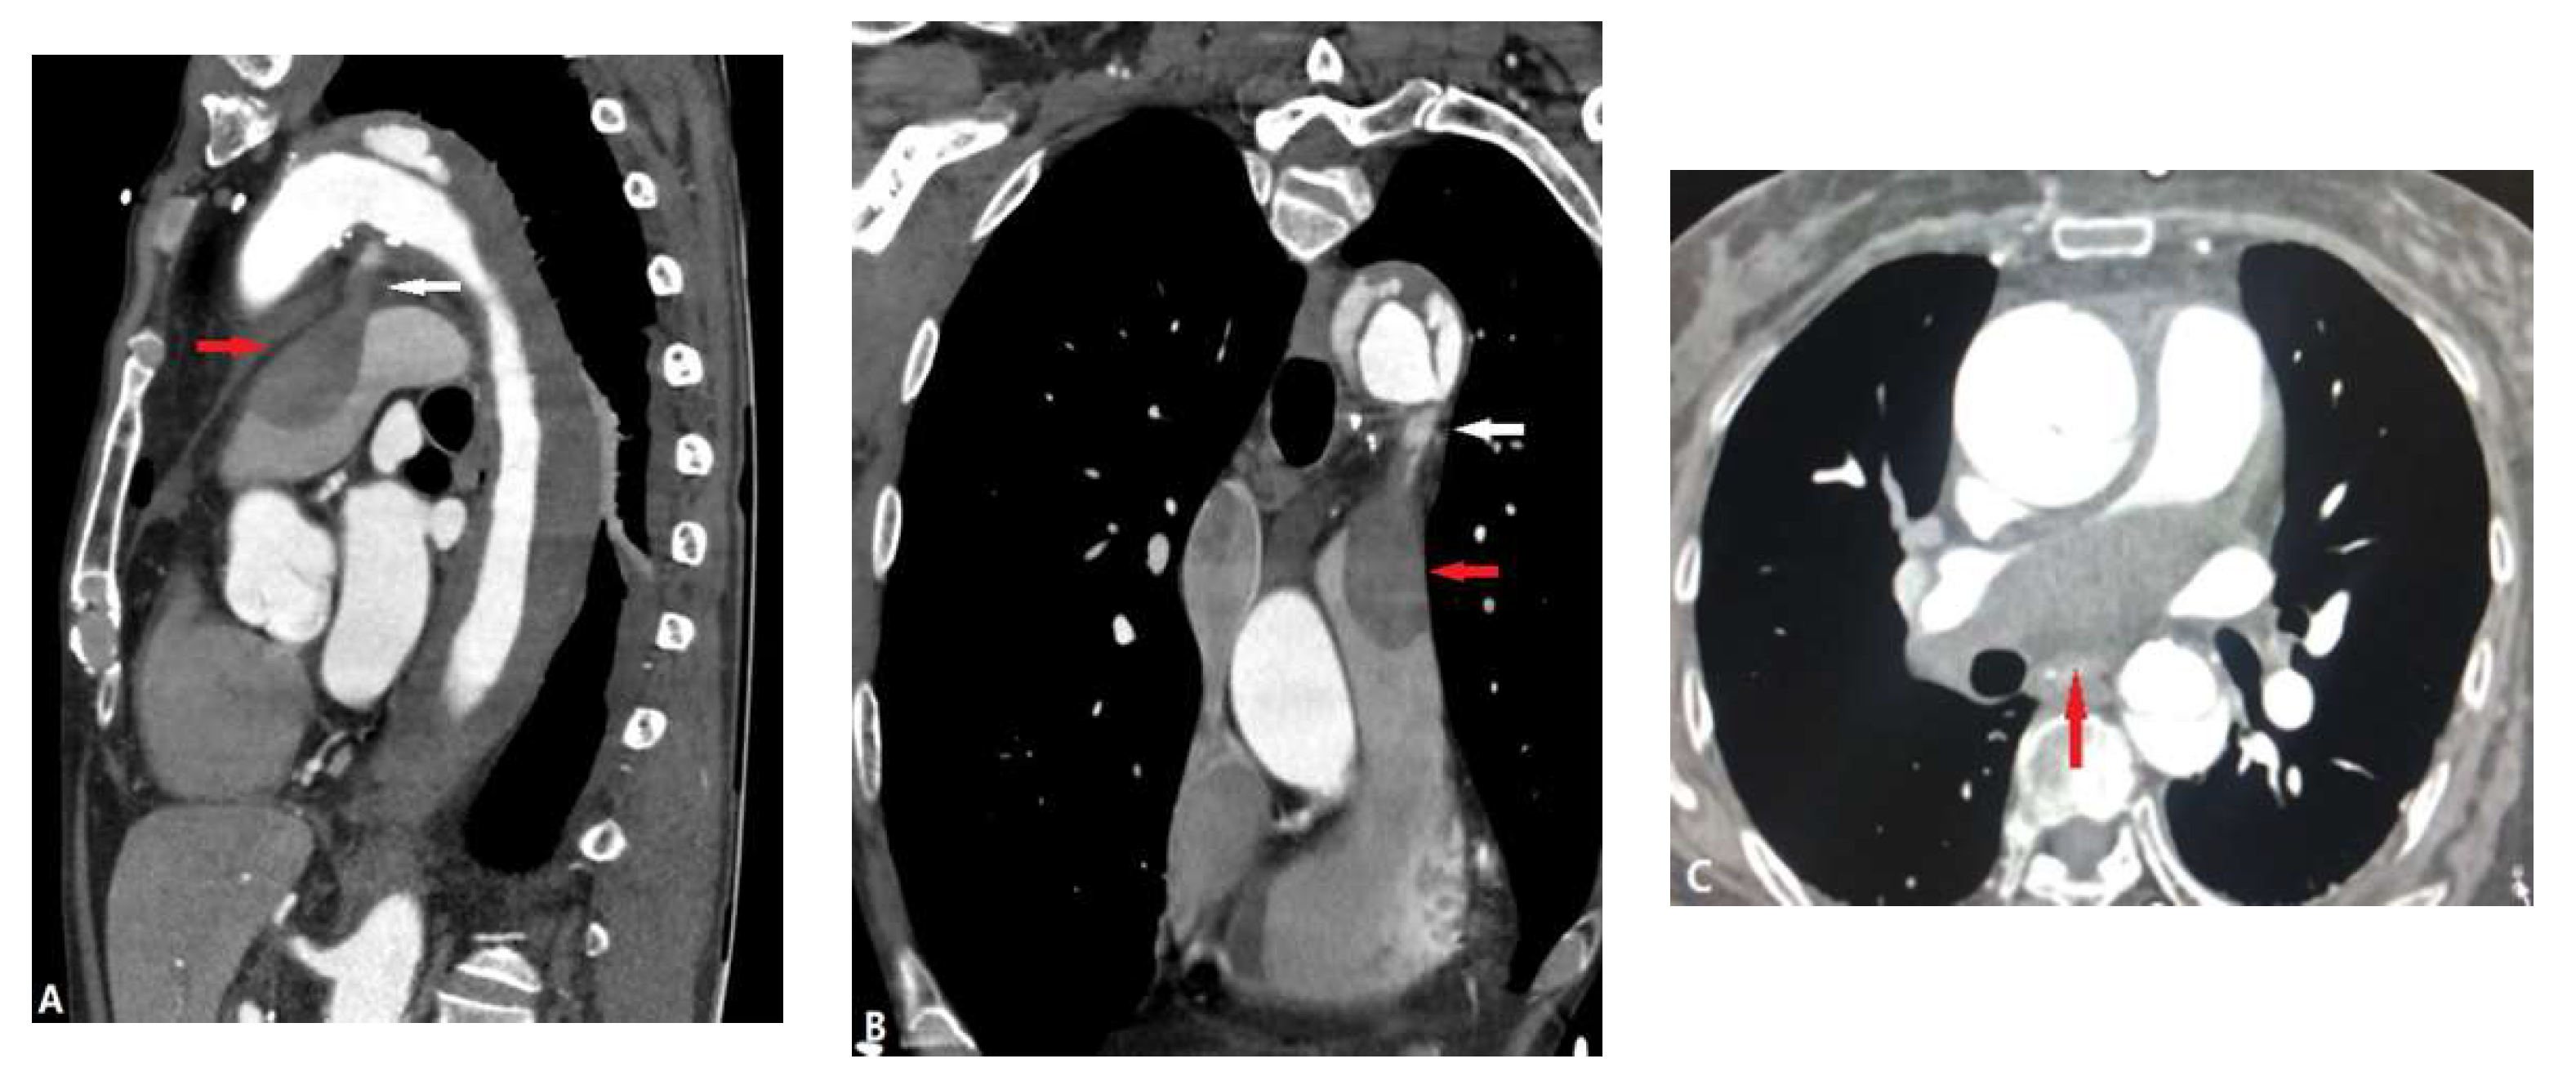

3.1.6. Pulmonary Artery Sarcoma

3.2. Vessel Wall Lesions

3.2.2. Arterial Dissection (AD)